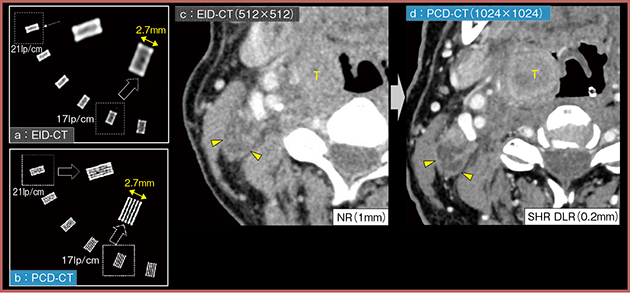

図1は,従来CT(EID-CT)とPCD-CTの比較であるが,PCD-CTではファントムの微細なスリットが明確に分離して描出されている(a,b)。また,臨床画像(図1c,d)でも,PCD-CTは0.2mmと薄いスライスであるにもかかわらず,高分解能と低ノイズを両立しており,微小病変や微細構造の評価に有用である。

図1 EID-CT(512マトリクス,NRモード)とPCD-CT(1024マトリクス,SHRモード+DLR)の比較

従来CT(EID-CT)はリンパ節転移の辺縁が不整に見えるが,PCD-CTは0.2 mmスライスで高分解能と低ノイズを両立し,リンパ節転移辺縁と周囲脂肪織との境界を詳細に評価可能(▶)